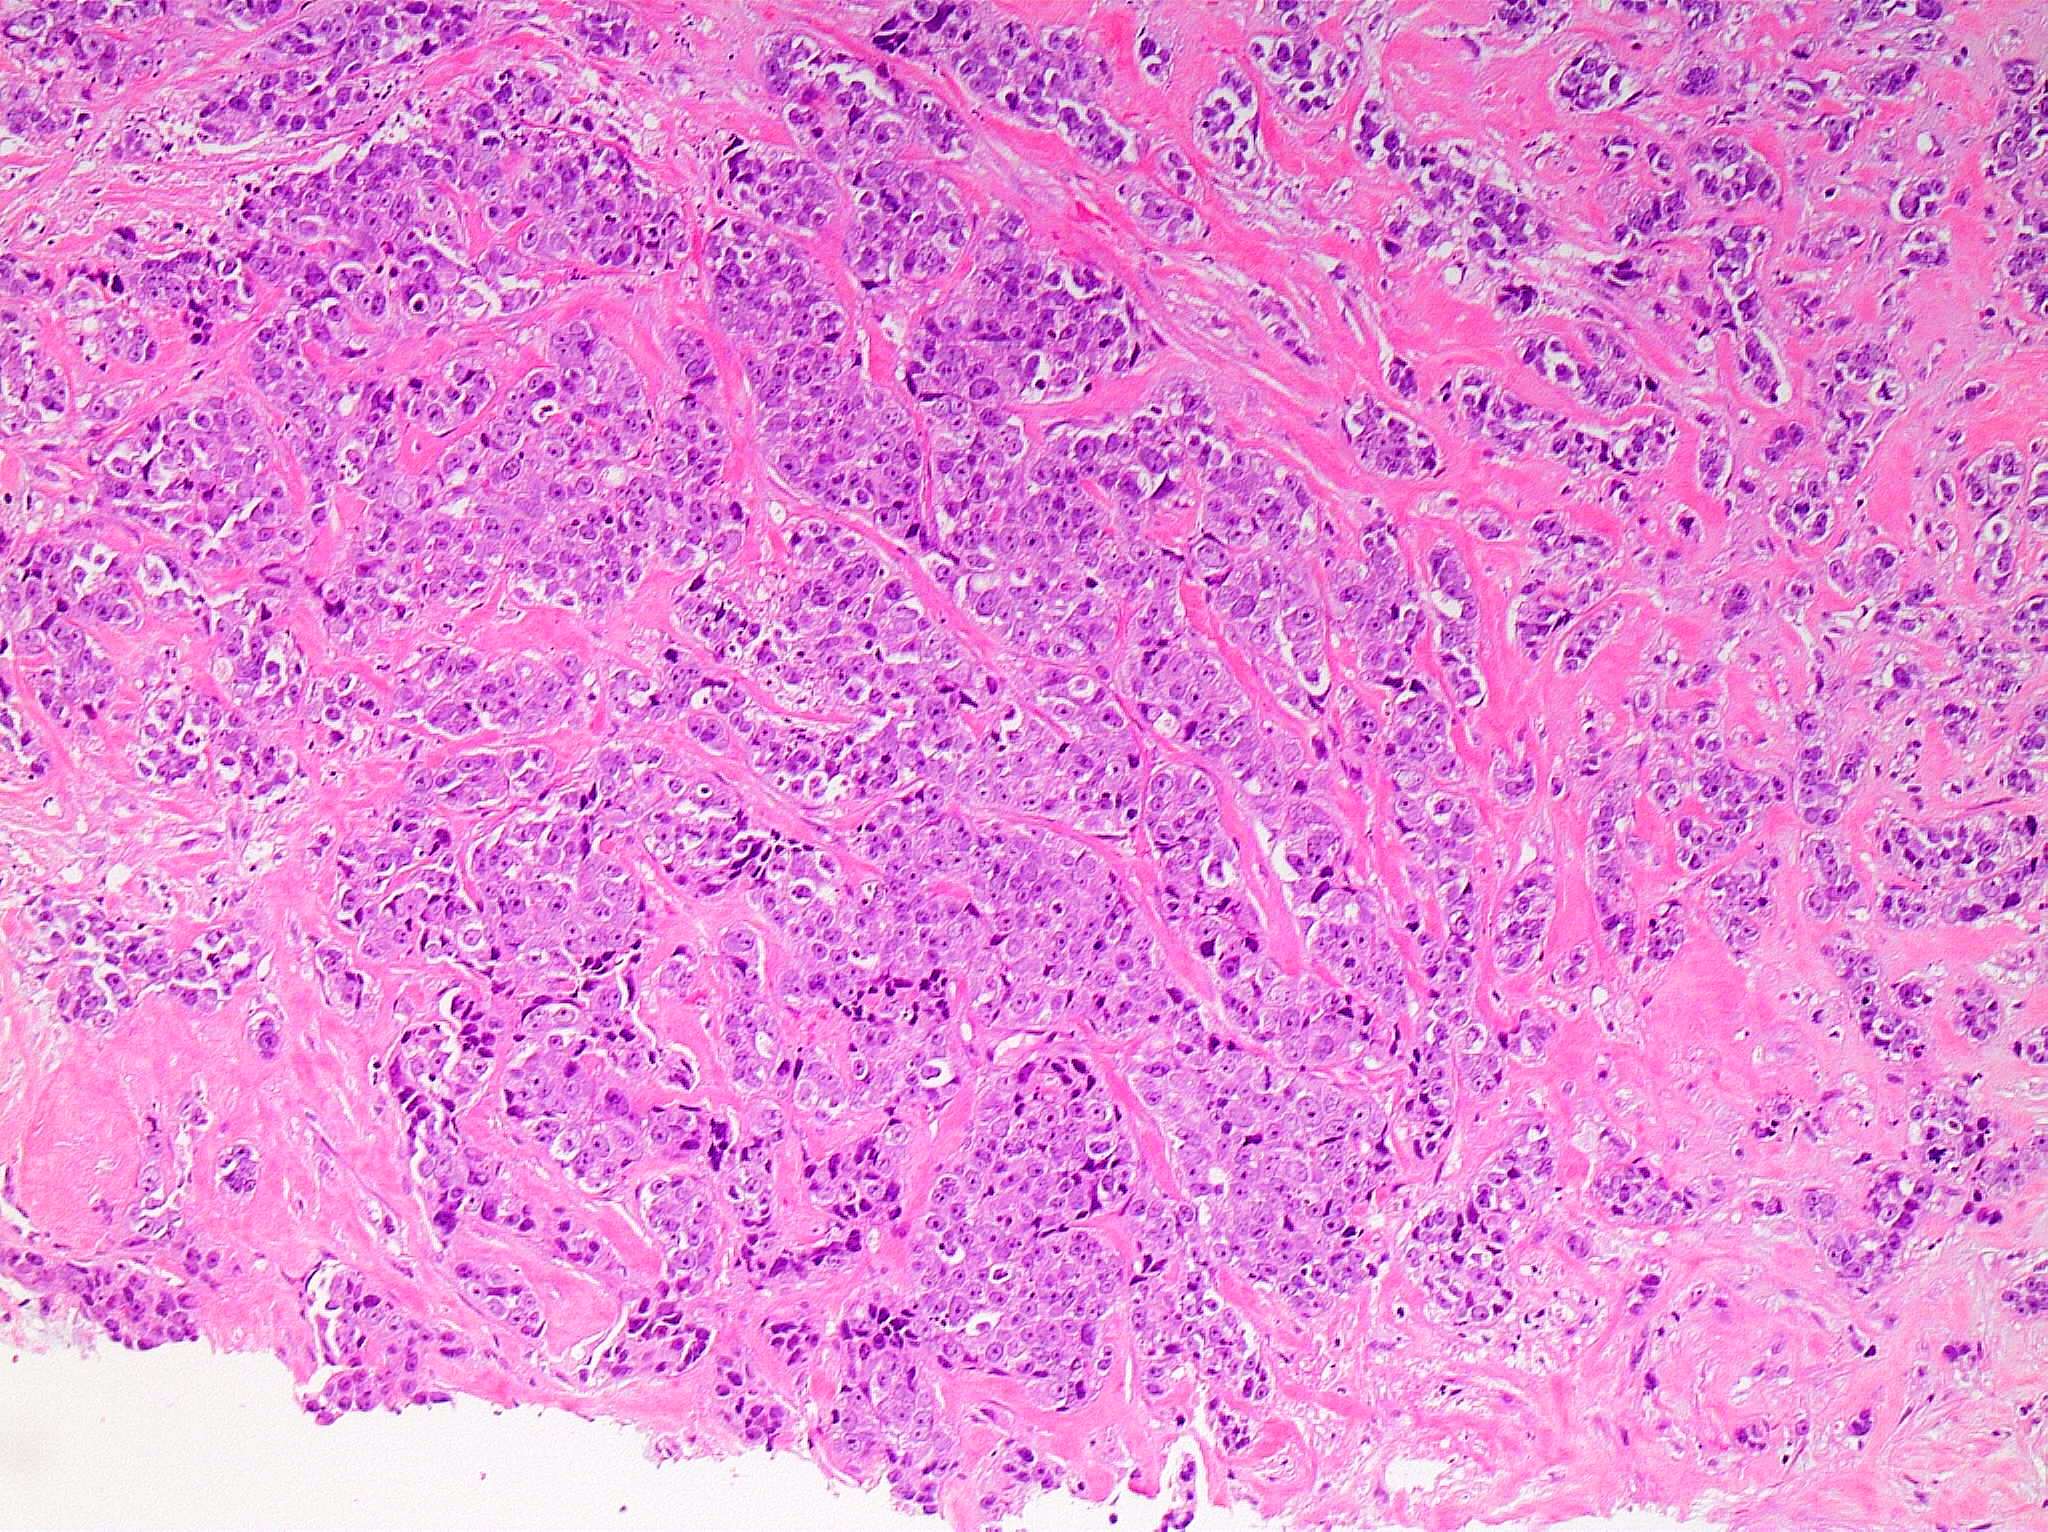

Microscopic (histologic) images

Contributed by Julie M. Jorns, M.D., Kristen E. Muller, D.O., Gary Tozbikian, M.D. and Emad Rakha, M.D.

- Histological features of IBC NST vary considerably from case to case and even within the same case

- Margins vary from highly infiltrative, permeating the surrounding tissue, to continuous pushing margins

- Architecture varies from sheets, nests, clusters, cords or individual cells (but lacks the cytomorphological characteristics of invasive lobular carcinoma)

- Tumors characterized by small cancer nests accompanied by marked fibrosis (desmoplastic / scirrhous); this type diffusely infiltrates the surrounding tissue as an irregular shaped spiculated mass

- Calcification in 60% of cases, variable necrosis

- Elastosis involves stroma, wall of vessels and ducts and causes grossly noted chalky streaks